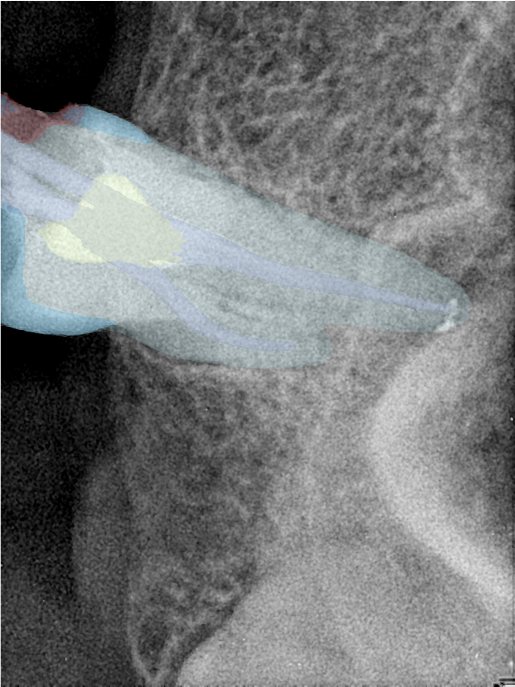

CR/DR 牙齿分割阶段记录

当前进展

- 完成了 CR/DR 牙齿相关分割训练

- 当前结果已经达到阶段预期,但仍有细节问题需要继续处理

相关测试

遇到的问题

- 训练过程中出现过 mask 下移问题

- 部分结果会出现 box 填充异常

- mask 边缘仍然有比较明显的锯齿感

参考

第二版算法问题测试